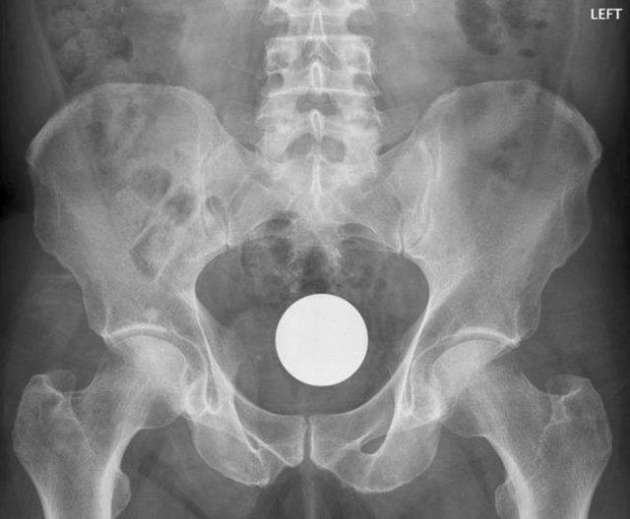

İÇİNDEKİ ŞEYE RÖNTGEN UZMANLARI ŞOK OLDU!

RÖNTGEN UZMANLARI ŞOK OLDU!

,Dünyada çekilen bu röntgenler hem röntgen uzmanlarını hemde görenleri şok ediyor...